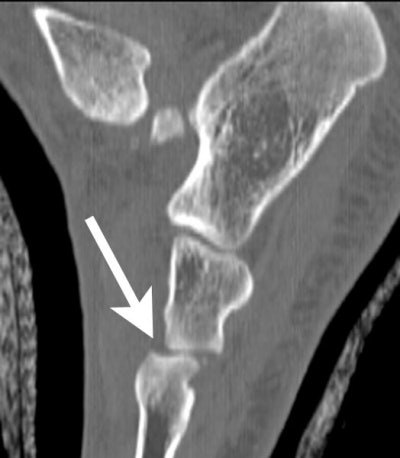

| Sagittal reformatted image through the lateral aspect of the foot shows inferior subluxation of the cuboid (arrow) relative to the fourth metatarsal. |